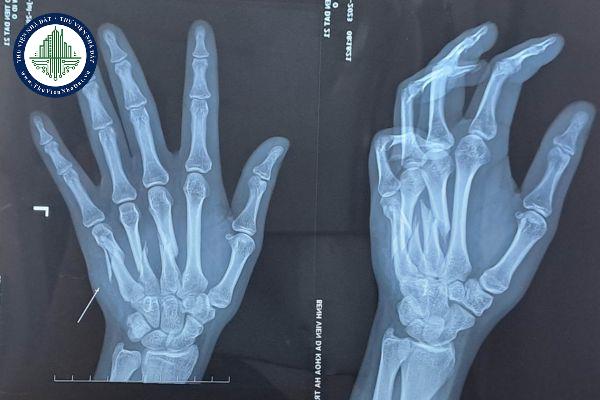

Gãy xương bàn tay

Gãy 1 xương bàn tay thì tỷ lệ tổn thương bao nhiêu %?

Em bị tai nạn nên bị gãy một xương mu bàn tay thì tỉ lệ thương tật là bao nhiêu phần trăm vậy ạ?